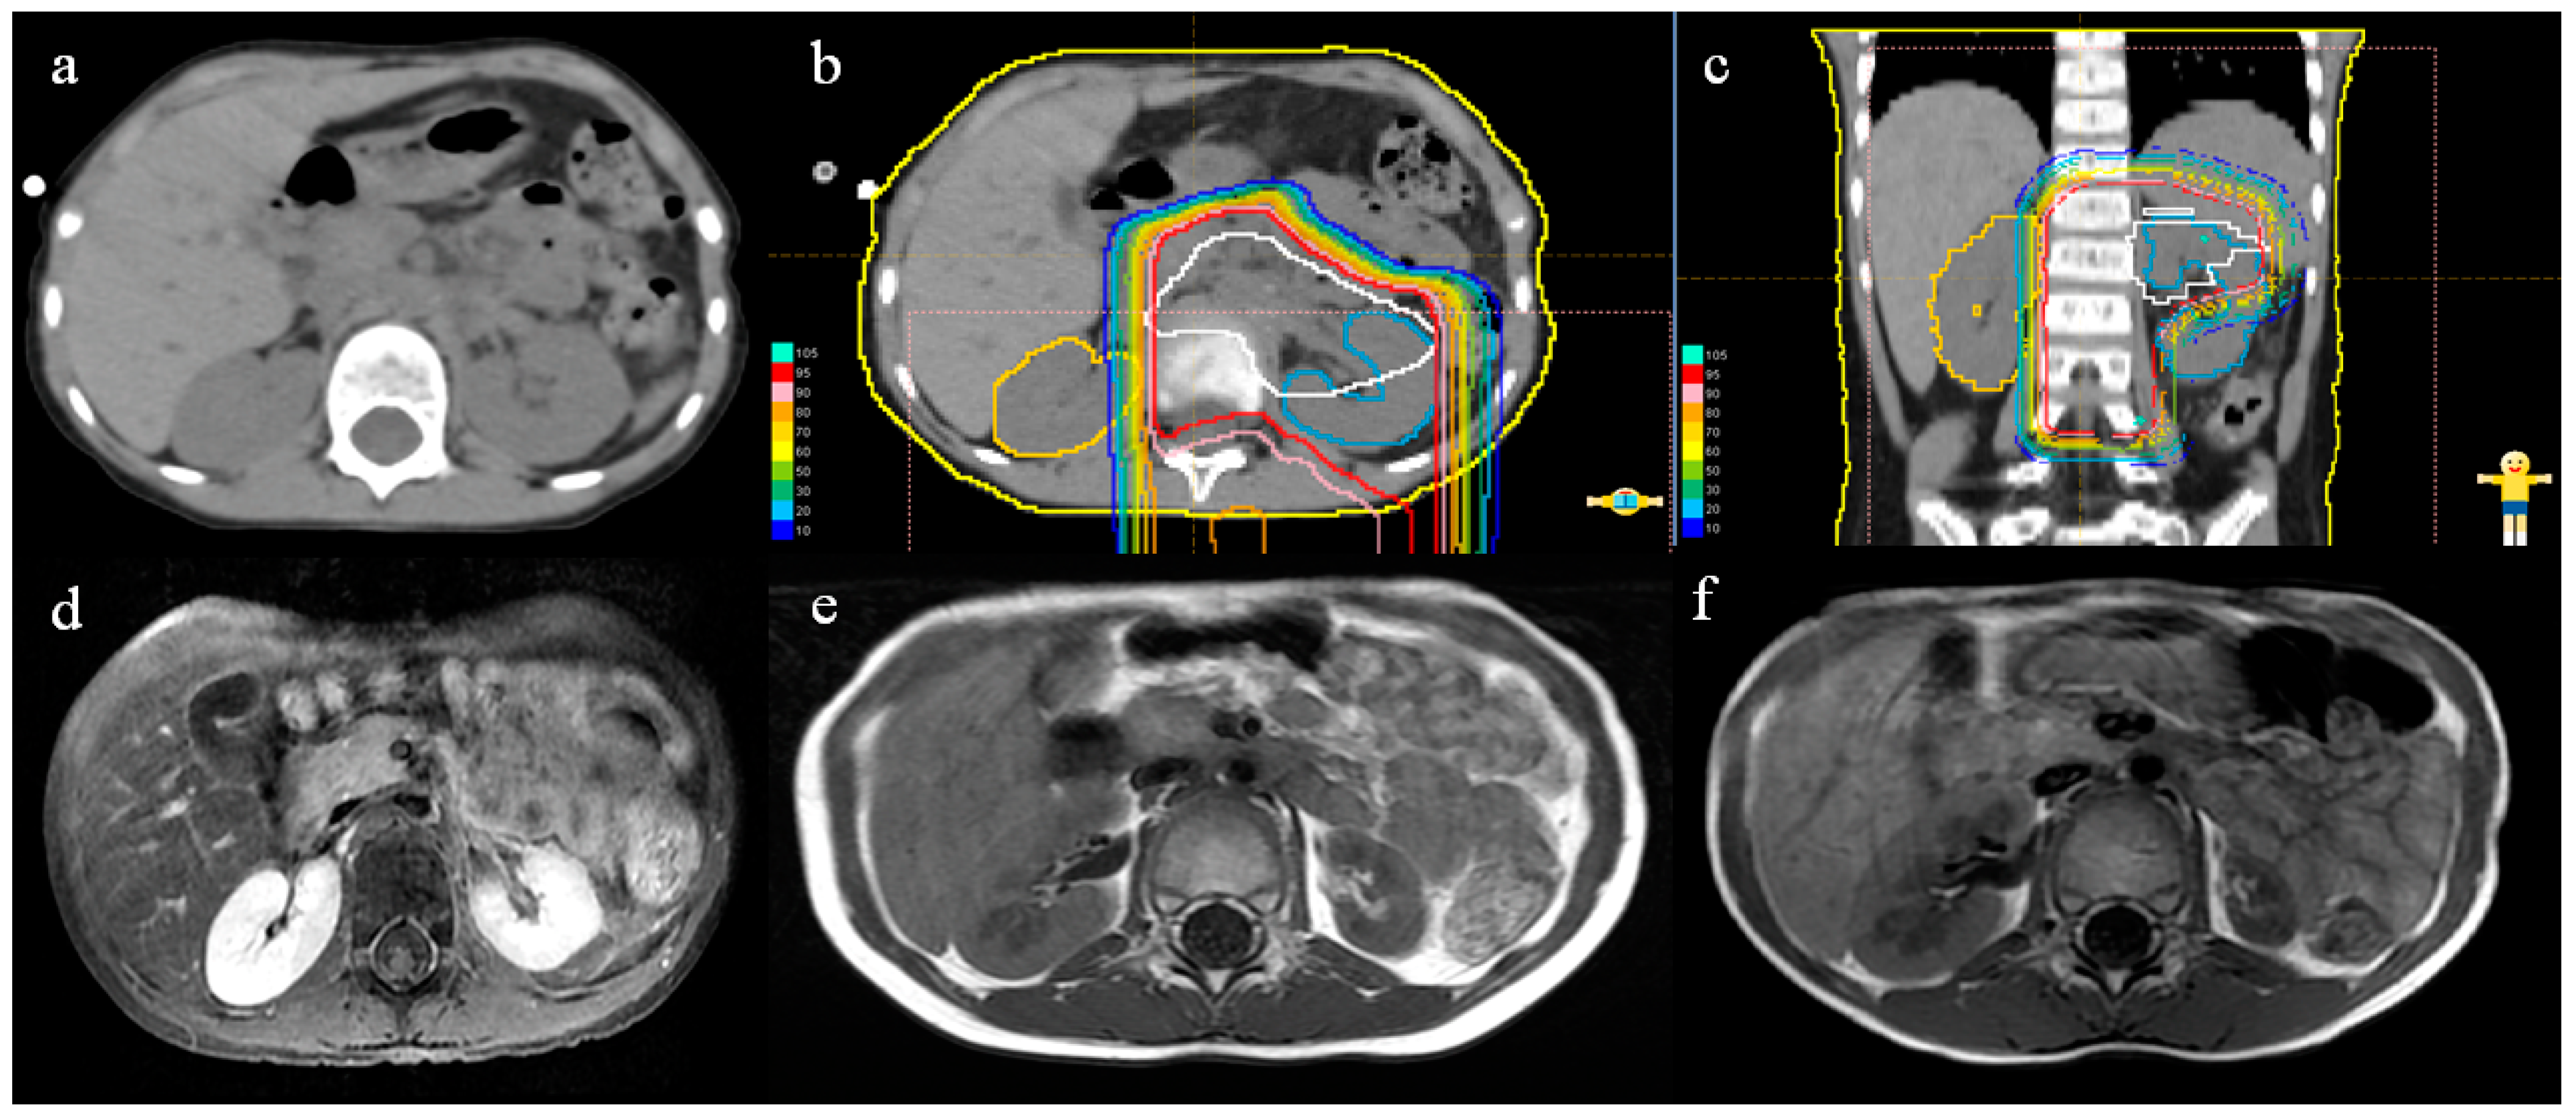

2.2. Proton Beam Therapy

3.2. Renal Volume Changes and DVH Analysis